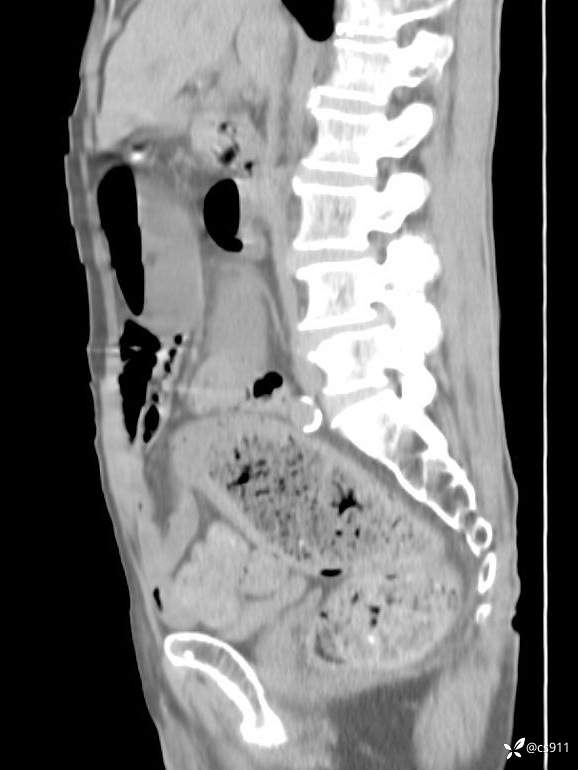

急腹症之急诊CT,原因?答案公布

男,77岁,腹痛、腹胀伴恶心呕吐1天。呕吐胃内容物,非喷射性呕吐,有咖啡色样胃内容物,诉有胃穿孔病史。查体:全腹平,下腹部压痛,全腹无反跳痛,叩诊呈浊音,移动性浊音阴性,肠鸣音减弱,1-2次/分。肛检:直肠未扪及明显肿物,可触及大量粪块。

血淀粉酶(AMY) HH 1859 U/L 35-135

癌胚抗原(CEA) H 27.44 ng/ml 0-5